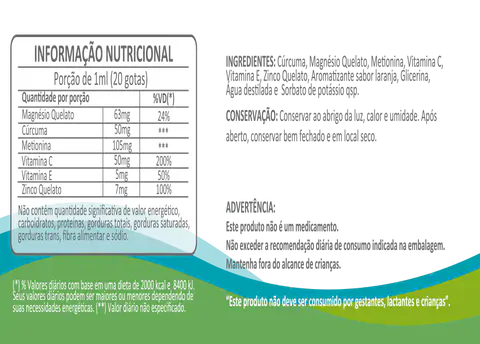

CONHEÇA O FÍGADOZEN

FÍGADOZEN é uma associação de ervas medicinais que trazem diversos benefícios à saúde.

O FÍGADOZEN PARA LIMPEZA DO FÍGADO garante ao seu fígado o cuidado e atenção necessários para se recuperar, além de melhorar drasticamente sua saúde e bem-estar.

OS PRINCIPAIS INGREDIENTES DO FÍGADOZEN

Descubra os ingredientes naturais que fazem do FÍGADOZEN um suplemento eficaz para a saúde do fígado.

Cúrcuma

Ajuda na desintoxicação do órgão, potencializando sua capacidade enzimática de limpar o organismo e evitando problemas no fígado.

Vitamina C

Tem importante papel no metabolismo e transporte de lipídios, atenuando a esteatose hepática.

Vitamina E

É um excelente antioxidante, aumenta as defesas do organismo e diminui a inflamação no fígado.

Magnésio

Essencial para melhorar a função hepática e contribui para a recuperação do fígado.

Metionina

Intervém no metabolismo das gorduras, reduzindo a sua acumulação no fígado e nas artérias.

Zinco

Colabora no bom funcionamento do sistema imunológico, participa da síntese e degradação dos carboidratos, lipídios e proteínas, e tem função antioxidante.